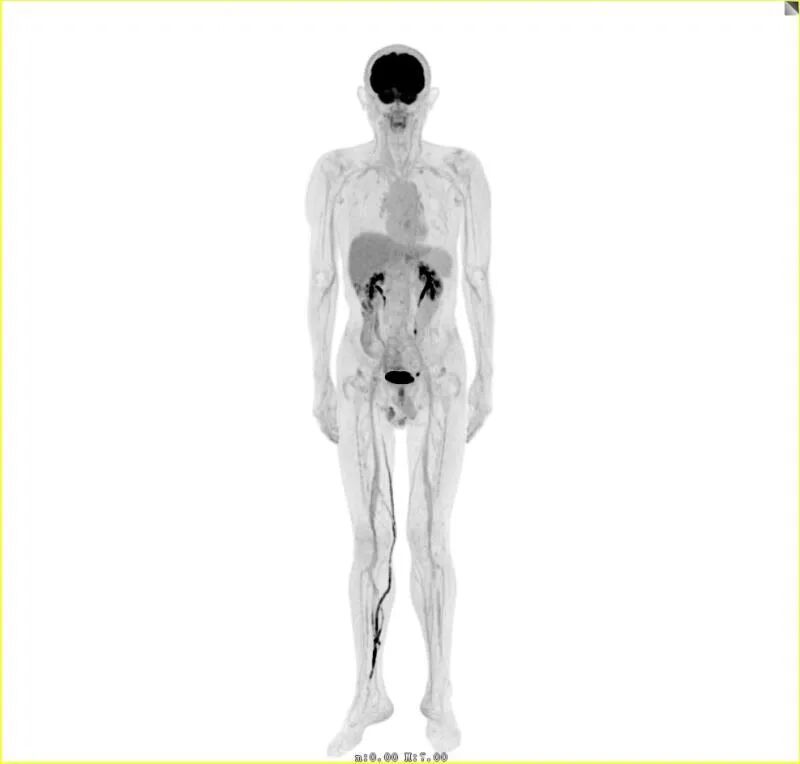

这就是刚刚在仁济医院完成装机的全景动态PET-CT成像系统uEXPLORER探索者,也就是大名鼎鼎的“人体哈勃望远镜”,它曾被英国《Physicsworld》杂志评为“2018年全球十大科学突破”。

这台2米长的全景动态PET-CT成像系统安装在核医学科,可一次实现整个人体的全景采集,并完成所有组织和器官同时成像。

只需要一个床位,探索者PET/CT即可借助于其超高灵敏度和超大的扫描视野在2-3分钟内完成全身采集,且扫描时产生的辐射剂量降低至传统设备的1/40。同时它首次实现了全身多组织器官的高清动态成像,不再局限于传统静态代谢过程3D成像,而是在此基础上新增一个“时间”维度,从而实现4D全景成像,在微小肿瘤病灶检出、神经系统疾病、心血管疾病及部分非肿瘤病变的诊断中具有独特优势。